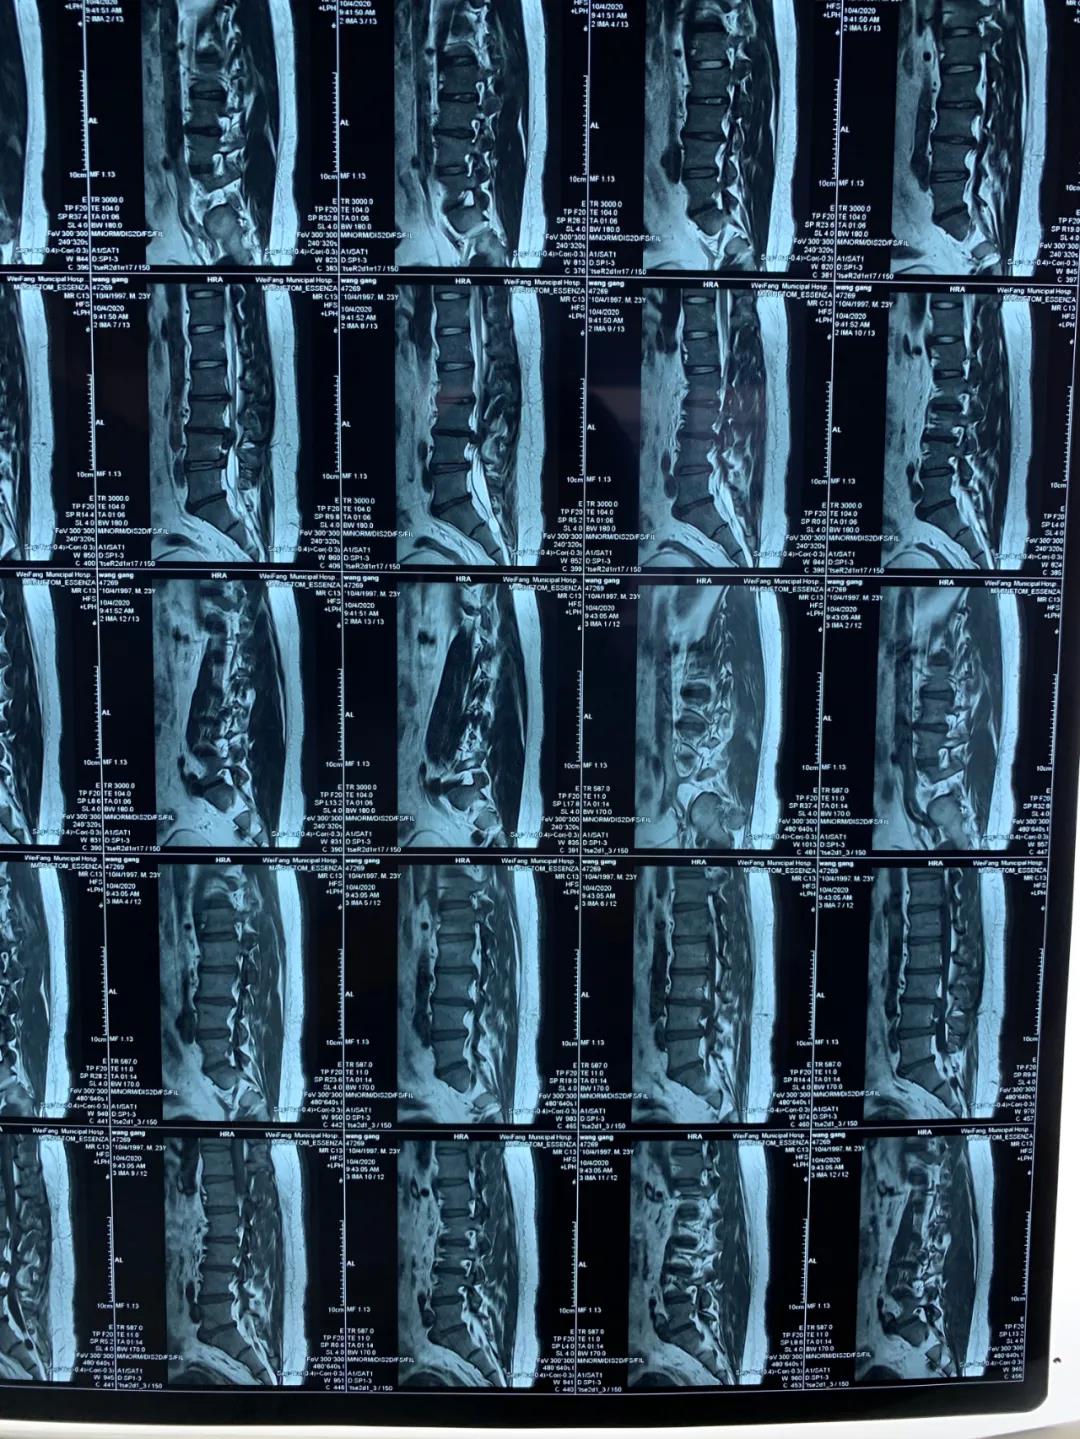

今年23歲的王先生因腰痛伴雙下肢放射痛及麻木不適2年加重5個月入院,入院后依據(jù)詳細查體和完善相關檢查,診斷為:腰椎間盤脫出癥,磁共振提示腰椎間盤巨大脫出。